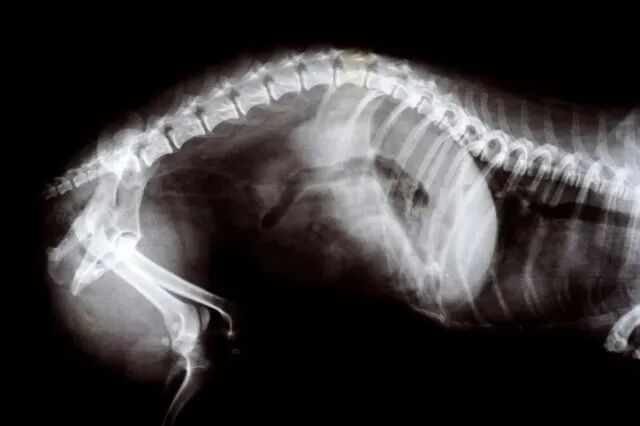

而经过详细的检查之后,医生发现豌豆的状况比他们预想的还要糟糕。

豌豆的腿部、臀部和骨盆有多处擦伤和骨折,鼻骨骨折,并且多处内脏受损,肺部塌陷!

这样的伤害放在任何一个成年人的身上都是致命的,更何况这只是一只刚出生不久的小奶猫!